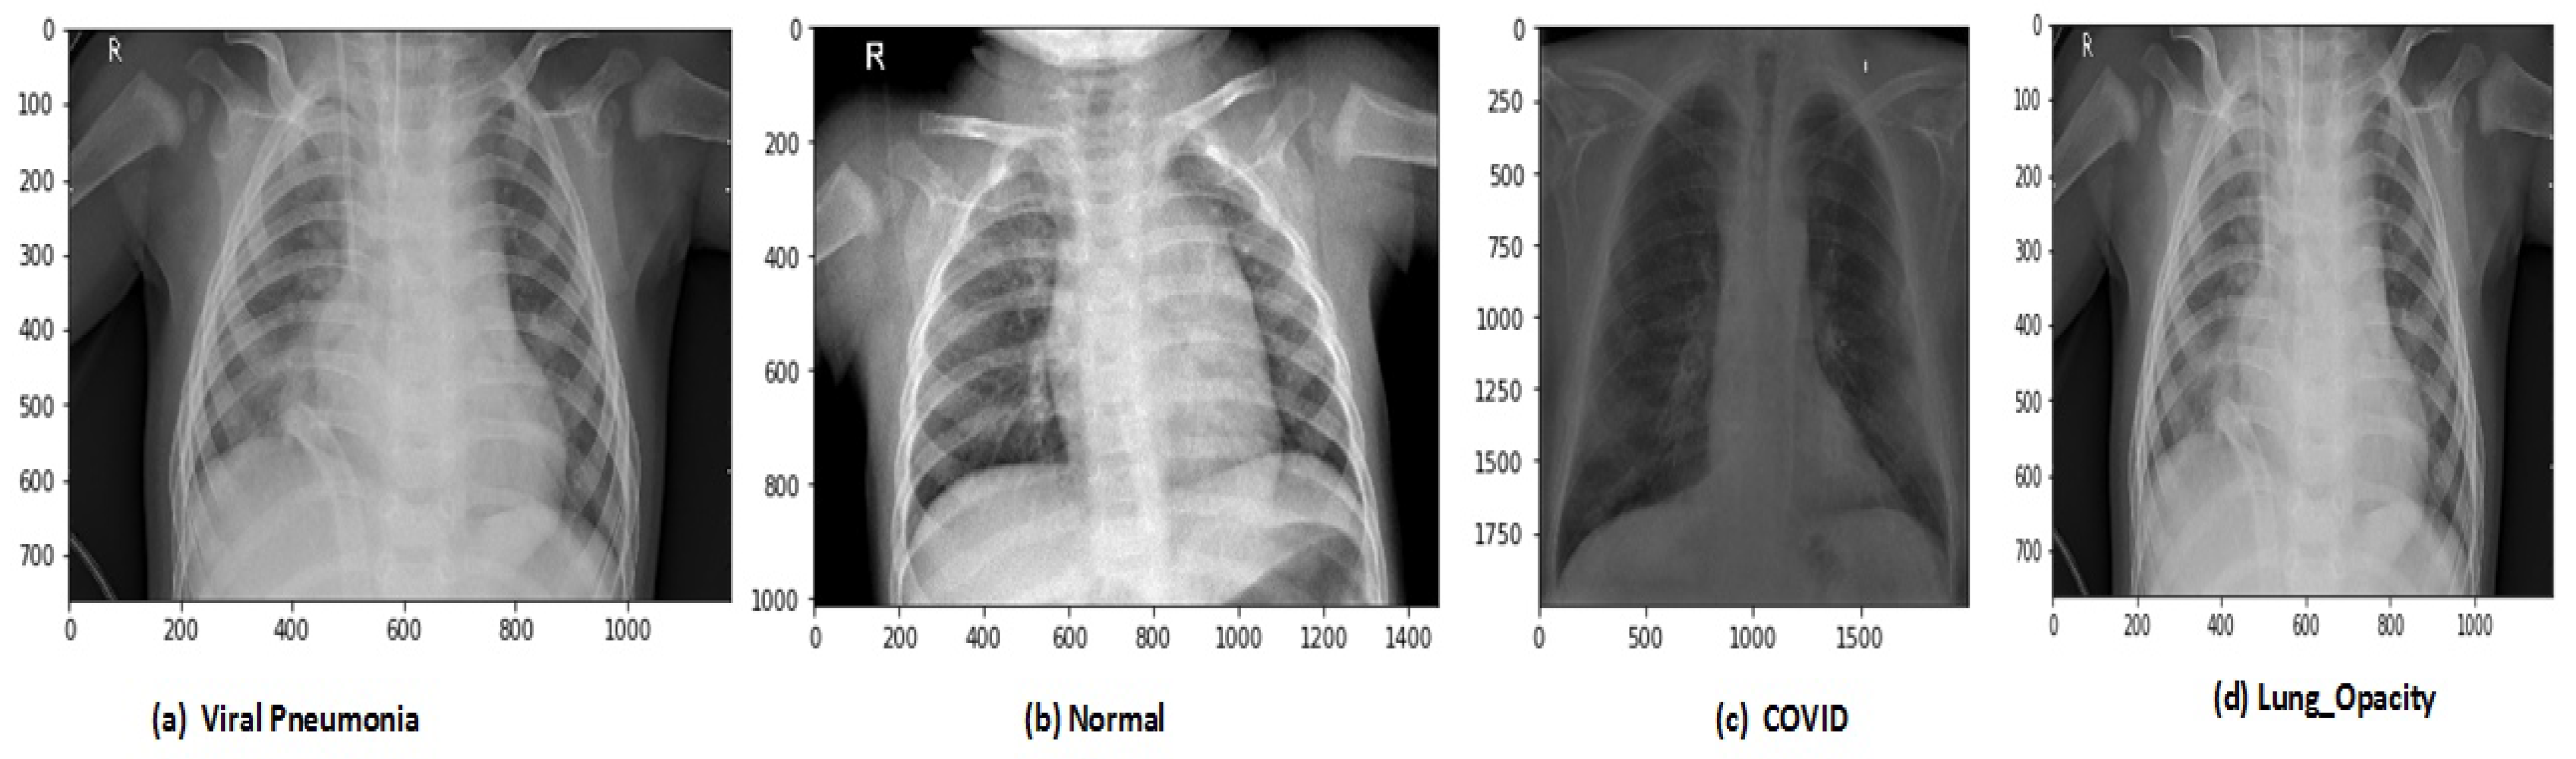

After data augmentation, the images in the new dataset are 12,864. The proposed model has trained on original and augmented data sets, respectively, for all experiments. The holdout cross-validation method has used for the training and validation process in the proposed model because the data sets are now large enough so it will not make computational complexity problems and model will fit exactly and will generate high performance. The images of CRD and CXI datasets are shown in Figure 3 and Figure 4.

Figure 3.

Types of chest X-ray images in CRD data set.

In this study, two data sets are used for the evaluation our model. The COVID-19-Radiography-Dataset (CRD) is a database of chest X-ray images for COVID-19 positive cases along with Normal, Viral Pneumonia images, and Lung Opacity. The data set has included 3616 COVID-19 positive cases, 10,192 Normal, 6012 Lung Opacity, and 1345 Viral Pneumonia images. The OVID-19-Radiography-Dataset is available on the Kaggle machine learning repository (https://www.kaggle.com/tawsifurrahman/COVID-19-Radiography-Database (accessed on 10 March 2021)). The second one chest X-ray (COVID-19, Pneumonia) (CXI) data set is achieved from Kaggle repository (https://www.kaggle.com/prashant268/chest-X-ray-COVID-19-pneumonia (accessed on 10 March 2021)). The data set has 6432 chest X-ray images, which belong to three classes (COVID-19, Normal, PNEUMONIA). The data set contain 576 COVID19, 1583 Normal, and 4273 PNEUMONIA images, respectively.

Two data set are used in this research for the evaluation of the proposed R2DCNNMC model. Before applying these data sets in the model we need to perform so pre-processing operations on both data sets that model suitable trained for effective performance. The COVID-19-Radiography-Dataset (CRD) is a data set of chest X-ray images for COVID-19 positive cases along with Normal, Viral Pneumonia, and Lung Opacity. This data set included 3616 COVID-19 positive cases, 10,192 Normal, 6012 Lung Opacity, and 1345 Viral Pneumonia images. The total images in the data set are 21,165.